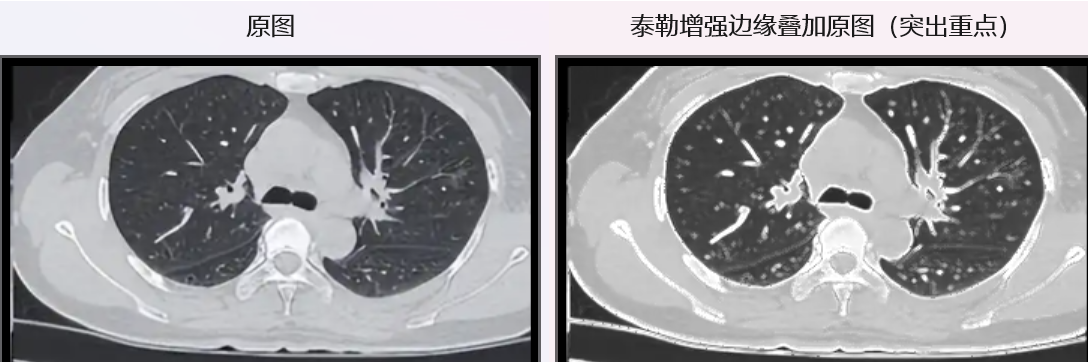

比对效果如下:

**Sobel检测:**只用到了一阶亮度变化率,所有细节全保留------包括物体轮廓、图像颗粒、传感器噪声,线条密密麻麻,有"流光感",艺术风格很强,但杂乱无章;

**泰勒增强:**结合了一阶变化率+二阶曲率,线条明显变少,很多细碎细节消失了,轮廓反而更突出、更干净。

泰勒增强怎么"丢了这么多细节"?这正式它的 "实用" 目标。

泰勒增强边缘,主动舍弃噪声细节,只强化稳定的真边缘, 线条干净,轮廓突出。

但是 Sobel的保留细节算法也更具有艺术视觉美:

我们看到的泰勒增强边缘里"丢失的细节",恰恰是它的核心价值------舍弃噪声,抓住本质。因此,理论本身没有绝对的"好"与"坏",关键看工程上怎么"用"。